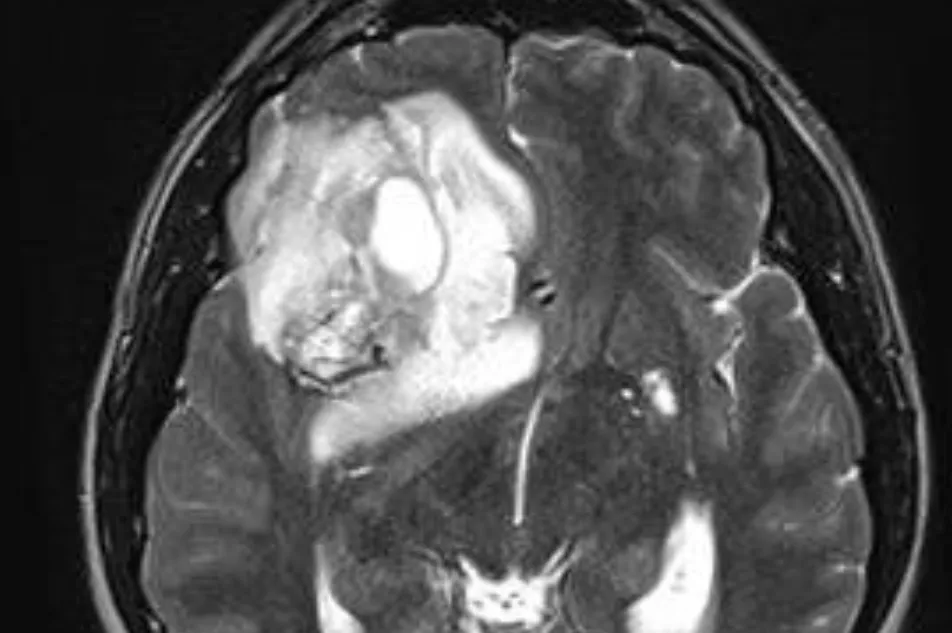

Les tumeurs gliales ou gliomes sont issues du cerveau lui-même, formées à partir des cellules gliales du cerveau. On distingue des gliomes bénins (astrocytomes, oligodendrogliomes, etc..) et les gliomes malins (astrocytome anaplasique, glioblastome) :

Les gliomes bénins sont souvent infiltrants, ne peuvent pas toujours être guéris par la chirurgie seule et vu la possibilité de récidive, doivent être suivis régulièrement même après une intervention. Il n’est pas toujours nécessaire de les opérer de manière agressive et parfois une simple biopsie est suffisante. Leur pronostic est en général assez favorable.

Les gliomes malins sont nettement plus agressifs et leur pronostic est nettement plus réservé. L’astrocytome anaplasique et le glioblastome nécessitent soit une biopsie, soit le plus souvent une résection chirurgicale selon l’endroit où ils sont placés, puis souvent une chimiothérapie et/ou une radiothérapie. Ces tumeurs ont tendance à récidiver rapidement et même après seulement quelques mois pour le glioblastome.

Les tumeurs gliales ou gliomes sont issues du cerveau lui-même, formées à partir des cellules gliales du cerveau. On distingue des gliomes bénins (astrocytomes, oligodendrogliomes, etc..) et les gliomes malins (astrocytome anaplasique, glioblastome)

Les gliomes malins sont nettement plus agressifs et leur pronostic est nettement plus réservé. L’astrocytome anaplasique et le glioblastome nécessitent soit une biopsie, soit le plus souvent résection chirurgical selon l’endroit où il est placé, puis souvent une chimiothérapie et/ou une radiothérapie. Ces tumeurs ont tendance à récidiver rapidement et même après seulement quelques mois pour le glioblastome.